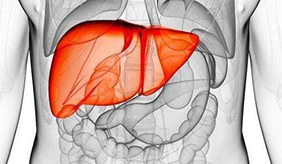

受肥胖和不良生(shēng)活(huó)方式的影响,现今患非(fēi)酒精性(xìng)脂(zhī)肪肝的人越来越多。该疾病如果得(dé)不到及时控制,会逐步恶化,最终甚至需要(yào)肝移植。MSN网(wǎng)站刊文,总结了(le)保护肝脏的6个关(guān)键(jiàn)......